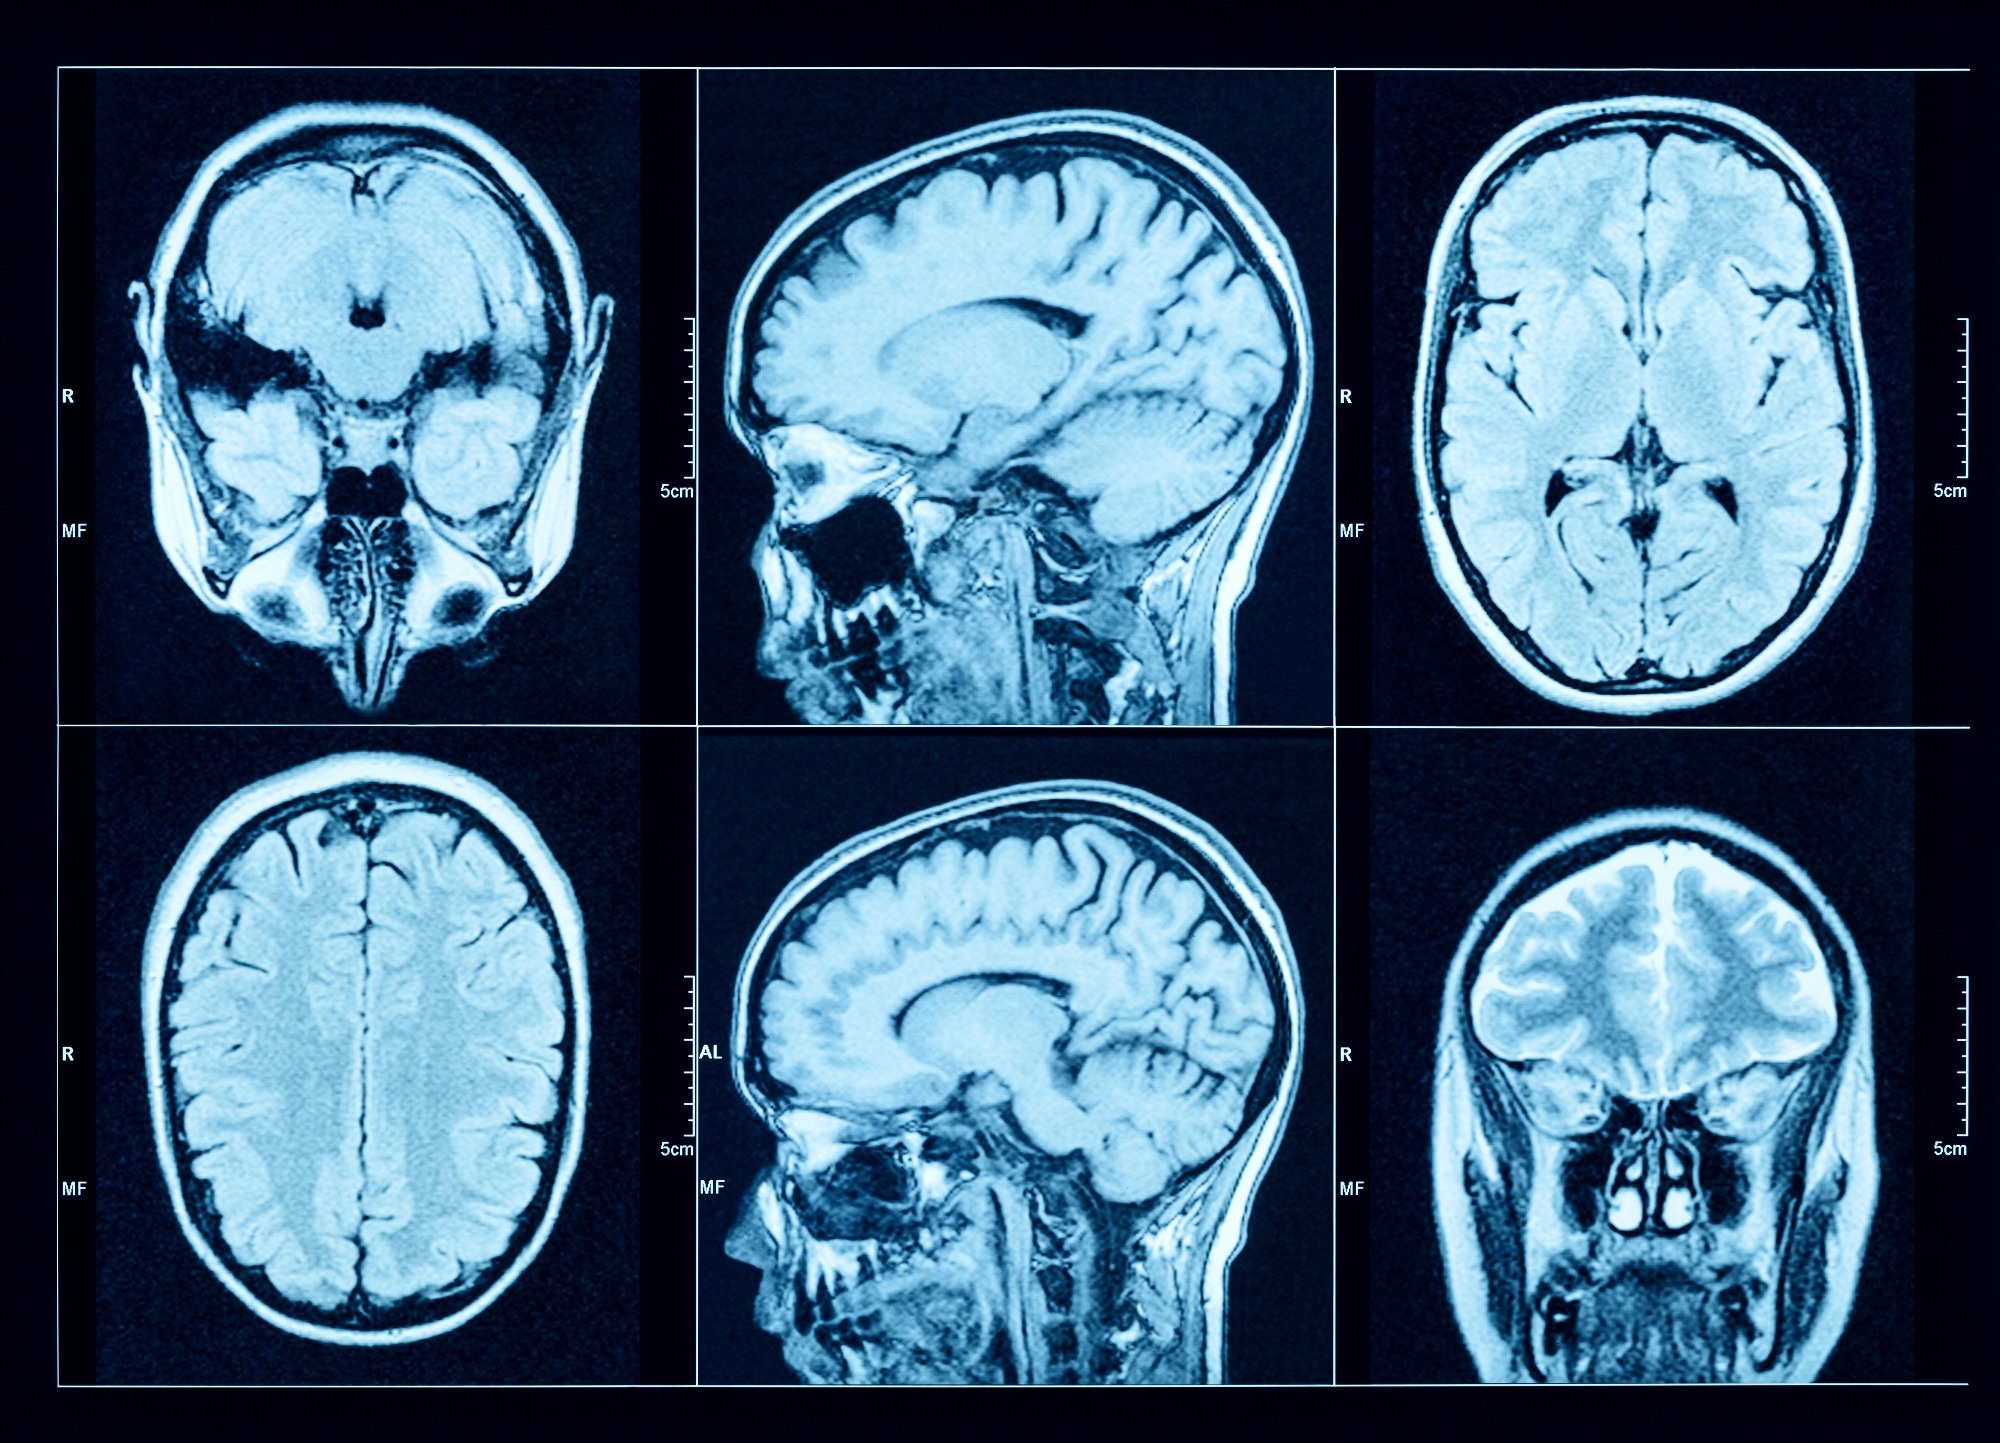

Study: Association of gout with brain reserve and vulnerability to neurodegenerative disease. Image Credit: Triff / Shutterstock.comStudy: Association of gout with brain reserve and vulnerability to neurodegenerative disease. Image Credit: Triff / Shutterstock.com

The team utilized 2,138 summary image-derived phenotypes (IDPs) that represented different estimates of brain structure using T1-weighted and T2-weighted-FLAIR structural imaging, diffusion MRI, and susceptibility-weighted MRI. FMRIB software library voxel-based morphometry (FSL-VBM) was used to determine the precise spatial distribution of relationships between gout and gray matter volume throughout the brain.

MRI results were used to determine whether causal relationships could explain the observed associations with brain structure. One-sample (gout) and two-sample (urate) linear MRI assessments utilizing summary statistics obtained from European participants were also performed.